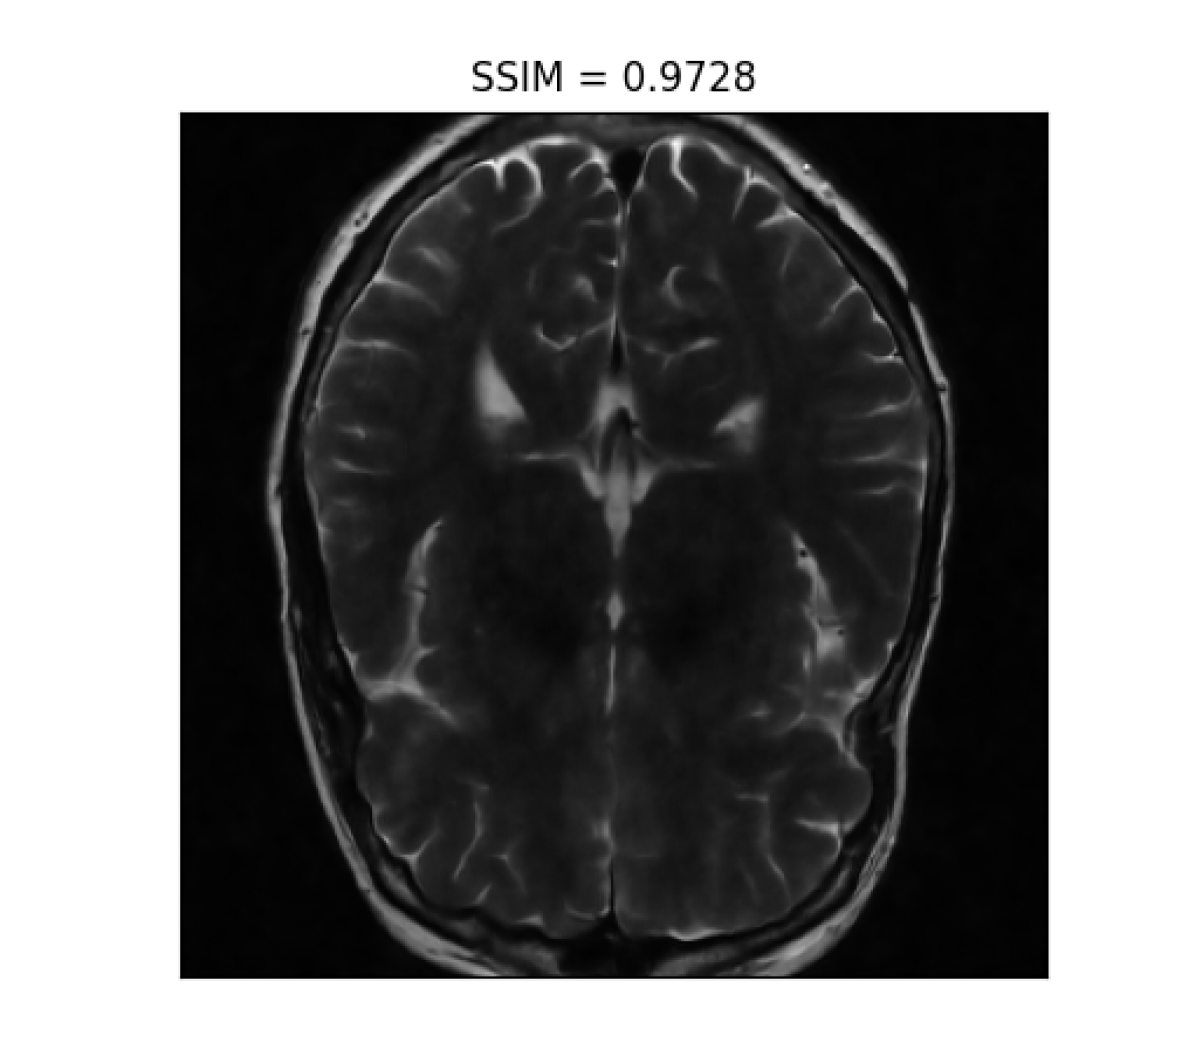

III-B2 Qualitative results

For visual inspection, we present the results of image reconstruction from data undersampled using SPARKLING trajectories generated for various target densities in Fig. 3 (T1subscriptT1\text{T}_{1}-w images) and Fig. 4 (T2subscriptT2\text{T}_{2}-w images). For the sake of space, we only report the best reconstruction results, i.e. with NC-PDNet. For T1subscriptT1\text{T}_{1}-weighted contrast, we show that all methods give similarly performing results, however 𝝆vdssubscript𝝆𝑣𝑑𝑠\boldsymbol{\rm\rho}_{vds} and 𝝆lbsubscript𝝆𝑙𝑏\boldsymbol{\rm\rho}_{lb} provide the best SSIM scores. Further, we observe that in this case, 𝝆vdssubscript𝝆𝑣𝑑𝑠\boldsymbol{\rm\rho}_{vds} is slightly better than 𝝆lbsubscript𝝆𝑙𝑏\boldsymbol{\rm\rho}_{lb}. On the contrary, for T2subscriptT2\text{T}_{2}-w contrast, 𝝆lbsubscript𝝆𝑙𝑏\boldsymbol{\rm\rho}_{lb} outperforms the other densities as reflected both visually in Fig. 4 and quantitatively (see Fig. 2).

Reference T2subscript𝑇2T_{2}-w Image (i) 𝝆vdssubscript𝝆𝑣𝑑𝑠\boldsymbol{\rm\rho}_{vds} (ii) 𝝆sbsubscript𝝆𝑠𝑏\boldsymbol{\rm\rho}_{sb} (iii) 𝝆lsbsubscript𝝆𝑙𝑠𝑏\boldsymbol{\rm\rho}_{lsb} (iii) 𝝆lbsubscript𝝆𝑙𝑏\boldsymbol{\rm\rho}_{lb}

Refer to caption Refer to caption Refer to caption Refer to caption Refer to caption

Figure 4: NC-PDNet-based image reconstruction for retrospective T2𝑇2T2-w imaging with slice 555 in file_brain_AXT2_200_2000019.h5 from validation data in fastMRI dataset for different target sampling densities.